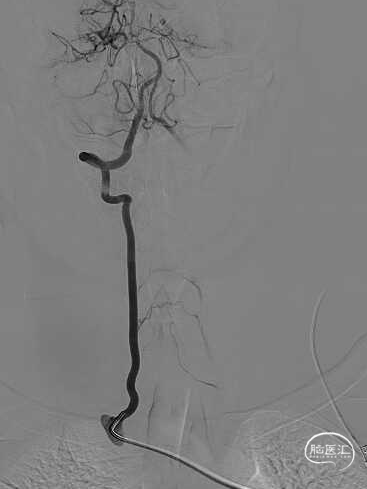

右侧椎动脉造影提示左侧锁骨下动脉盗血,左侧锁骨下动脉闭塞,近端残端较圆钝。

8F Guiding+5F MPA同轴置于左侧锁骨下动脉残端处,反复尝试Command 190cm及Command ES 190cm导丝配合Rebar-18微导管,导丝无法进入真腔,更换Connect 195cm导丝尝试后顺利进入真腔,使用小球囊预扩, Guiding跟到病变远端。

更换Supracore导丝,使用雅培 5*40mm Armada35 球囊扩张后在闭塞起始部植入8*29mm Omnilink支架。